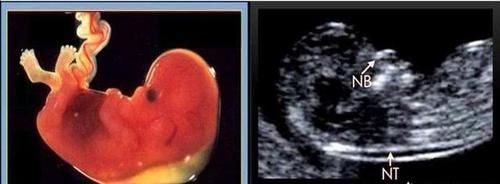

孕23周+2四维显示无鼻骨,做唐筛NT低风险,孩子能留吗?对于正常的胎宝宝来说,他们是有两块鼻骨的,在出生以后,两块鼻骨会逐渐的融合到一块,而胎宝宝的鼻骨通常在怀孕6周的时候就开始发育了,到了怀孕10周左右,胎宝宝的面部的骨骼部分开始骨化,所以在做NT检查的时候,胎宝宝已经能够看到鼻骨了,如果之后的四维彩超闲适胎宝宝鼻骨不清楚的话,孕妈妈们可以对照一下自己的NT检查,如果没有鼻骨,在NT检查的时候就会写出来的。

有研究表明,在没有鼻骨的胎宝宝当中,有25%左右的是21-三体综合征,就是我们常说的唐氏儿,还有约2.2%左右的是18-三体综合征,也属于一种染色体畸形,没有鼻骨的胎宝宝总体上出现染色体异常的几率是正常胎宝宝的21倍之多。那么,是不是说,如果查出来胎宝宝没有鼻骨,是不是这个胎宝宝就不可以要了呢?

当然不是。

在医学上,胎儿没有鼻骨其实只是一个超声“软指标”,也就是说,出现没有鼻骨的情况的胎宝宝可能是有问题的,但也可能是没有问题的,一般来说,12周以后胎宝宝的鼻骨就应该已经发育完全了,如果出现没有鼻骨的情况,孕妈妈是需要慎重对待的,有一部分没有鼻骨的胎宝宝还有别的方面的问题,那么畸形的几率会更加的大。